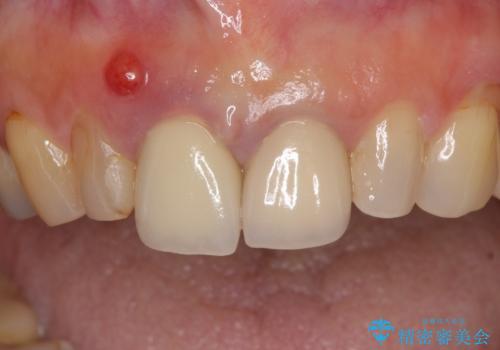

- 神経の抜いた歯が折れてしまい、痛みを感じて来院された患者様です。

折れてしまった歯は抜歯せざるを得ないため、抜歯と同時に仮歯を装着し、その後オールセラミックブリッジにて補綴することとしました。

折れた前歯を抜歯すると、歯肉が痩せてしまい、ブリッジの形態の審美性が失われることがあります。仮歯を調整することで審美回復が必要であるか判断しますが、今回は歯肉移植を行うことなく補綴治療を行いました。